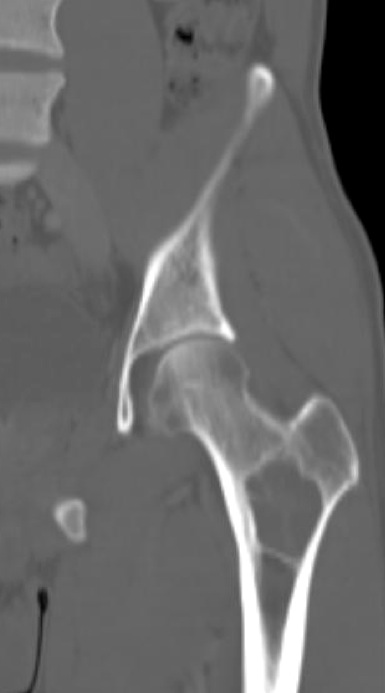

Figure 2 for case fibrous dysplasia ( RID3738 )

Figure 2